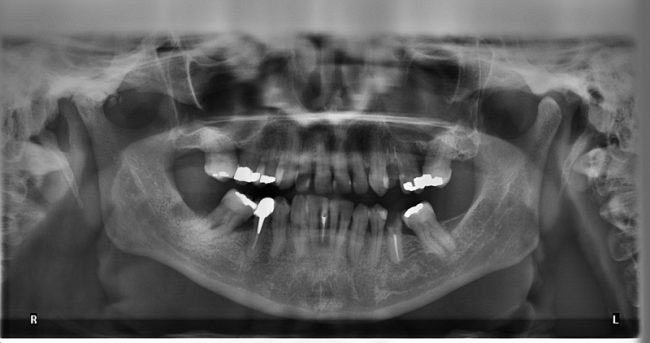

What is Periodontitis? Periodontitis, otherwise known as gum disease, is a serious bacterial infection of the gums. It is caused by bacteria and ranges in severity. Over time, periodontitis can lead to damage of the soft tissue, teeth, and bones, possibly resulting in the loss of teeth. This condition is treatable, and with care,…